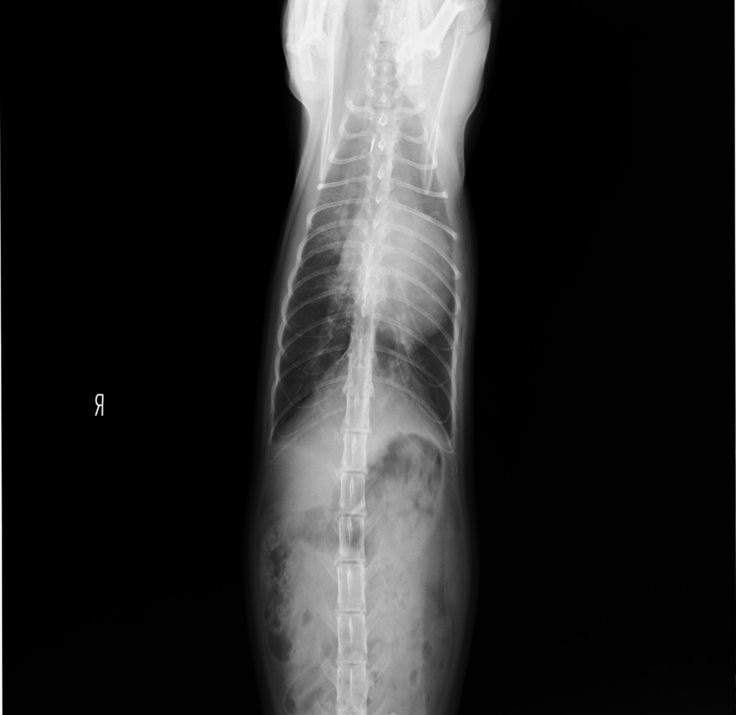

2019年5月頃

軽い咳が続き、心配になったので病院に連れていきました。

その時のレントゲン写真です。

この時は、肺が少し白いことから、気管支炎と診断され、

薬をもらい様子を見ることにしました。